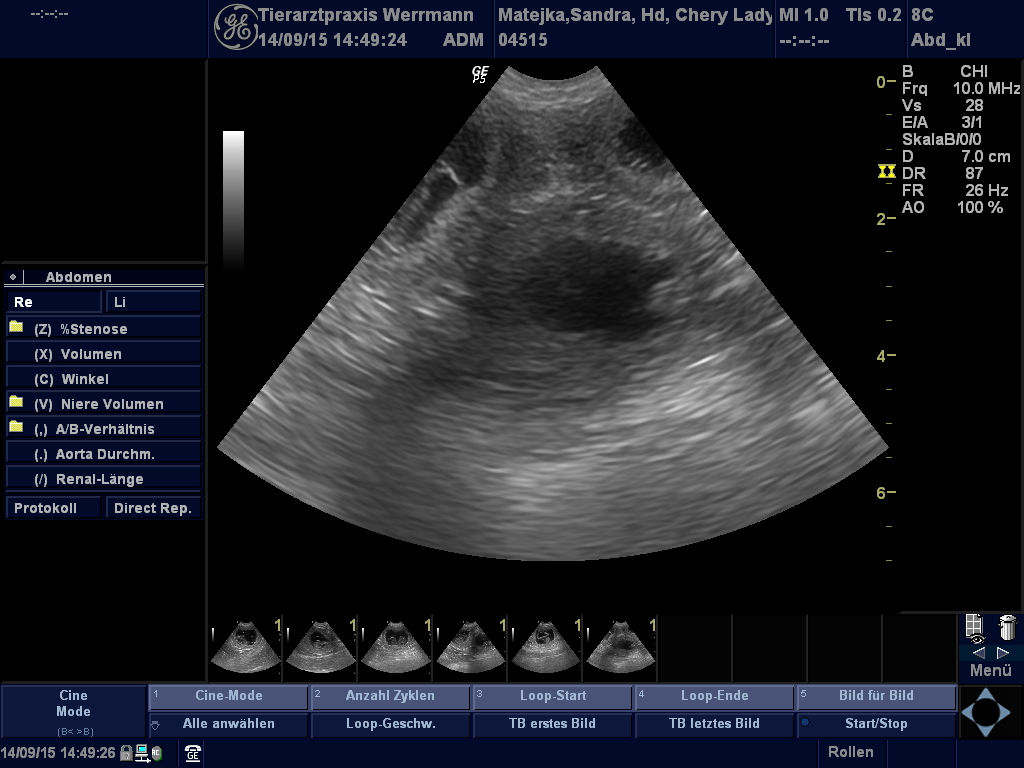

Ultraschallbilder